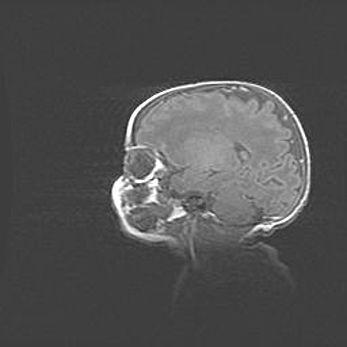

Наружная гидроцефалия с возможной атрофией височных областей.

Возраст: 28 дней

Вес: 3670 г

Пол: мужской

Окружность головы: 38 см

Срок гестации: 40 недель

Гидроцефалия головного мозга у новорожденных – это заболевание, которое характеризуется скоплением избыточного количества спинномозговой жидкости в желудочковой системе головного мозга в результате затруднения её перемещения от места выработки к месту поглощения в кровеносную систему или вследствие нарушения абсорбции. При открытой наружной форме гидроцефалии у новорожденных расширяются и переполняются субарахноидные пространства.

При нормотензивных  формах,  которые,  как  правило,  являются  следствием  перенесенных ишемических  повреждений  паренхимы  мозга,  возможно  сочетание микроцефалии  с нормотензивной гидроцефалией. В основе данных изменений лежит атрофия больших полушарий с преимущественной  локализацией  в  лобно-височных  областях.